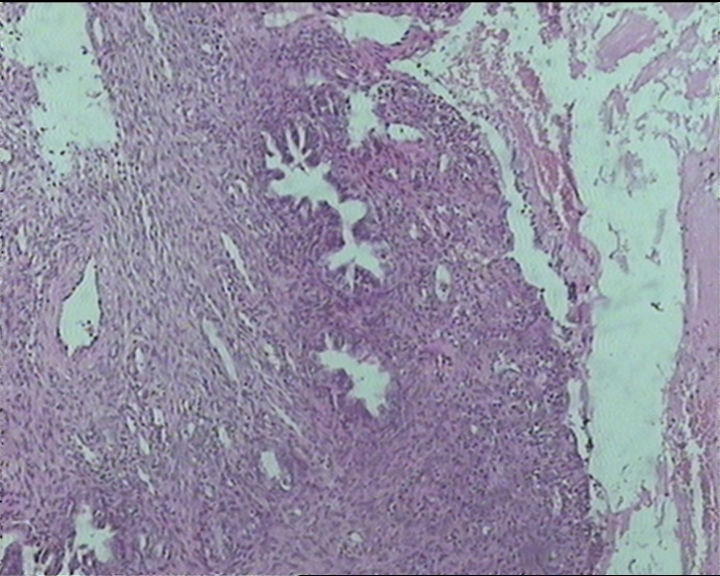

54岁女性,临床“宫颈息肉”送检;巨检:组织一块1。5*1CM,灰红。

输卵管粘膜化生

It is benign. Benign endocervical polyp with tubal metaplasia.

细胞及腺体均有异形,图6、11、16象有纤维间质反应,考虑高级别上皮内瘤变/原位癌,腺癌不能除外。

Sternberg病理学上诊断宫颈原位腺癌的标准是腺体的上皮去粘液分化,呈乳头状或筛网状增生,核分裂易见,这例显然达不到此标准。此例还是归入到腺上皮不典型增生为好。

杨老师说它是良性的,是个颈管内膜息肉伴输卵管上皮化生,良性